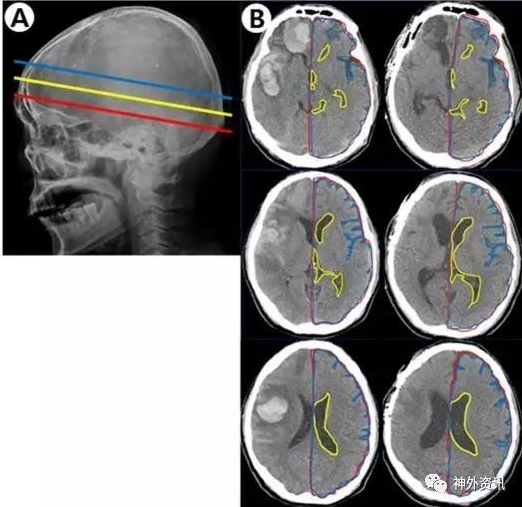

該研究收集作者所在單位2011年至2015年接受手術治療的自發性腦出血患者。研究對象的血腫位于幕上單側大腦半球;根據術前和術后3個月在頭顱CT軸位3個平面,即室間孔平面、透明隔平面和側腦室平面上的影像片(圖1)

計算發生出血對側的腦實質面積與同側顱腔面積之比以消除個體差異,分析與對側腦組織體積變化的相關因素。

總共納入44例患者,其中12例血腫清除后骨瓣復位,15例行血腫清除加去骨瓣減壓術,17例行血腫穿刺引流術。結果表明,所有患者術前與術后3個月CT圖像上,在室間孔、透明隔和側腦室3個平面的對側腦組織與同側顱腔面積平均比值,分別為92.3%比88.8%、90.3%比85.3%和86.9%比82.5%,差異均有統計學意義(P<0.001)。血腫破入腦室是導致對側腦組織體積縮小的最顯著因素(P=0.006);此外,入院時GCS評分低(P=0.016)和吸煙(0.039)也是對側腦組織體積縮小的獨立影響因素。